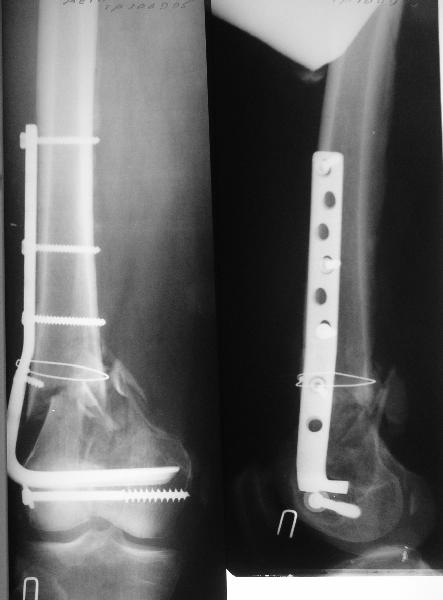

Удалили ластину без проблем. Выявилась значительная подвижность. В этих условиях сразу пропала мотивация к постепенной коррекции аппаратом. Попробовал восстановить длину, введя между отломками spreader. Отчасти удалось. Тогда защили рану, наложили спицевой дистрактор (2 спицы в дистальный отдел и 1 вверху). после этого был убран и спонгиозный винт. И сделали антгерадное штифтование, как говорится, "по принятой в

клинике методике".

Дополнительные доступы для введения гвоздя и проксимальных винтов понадобились, но они маленькие, по 1 см. Нижние винты ввели прямо между швами. Суставы дополнительно не травмировали, и даже ввели гвоздь не через f. piriformis, а через большой вертел.

Длину восстановили, возможно, даже с изьбытком, ну да динамизируем пораньше. Введенные в овальное отверстие дистальые винты имеют угловую стабильность. Снимки приложены. Заранее спасибо за критику и комментарии.

Довольно симпатично получилось. Не сомневался, что будет именно такой антеградный реостеосинтез.

Была ли педресация на столе после окончательной фиксации? Уверен ли ты, что "угловая стабильность" дистальных винтов позволит агрессивно заниматься разработкой движений в коленном суставе?

Nicely executed surgery with good planning resulting in great looking x-rays but not the best the way to deal with this fracture. Earlier fracture was having slight translation with no angulation and no instability, now ur fracture is distracted with potential instability as your construct is not the best suited to this place, so more likelihood of non union or complications.

Should have preferred a locking plate if at all u wanted to reoperate and

added copious bone graft.